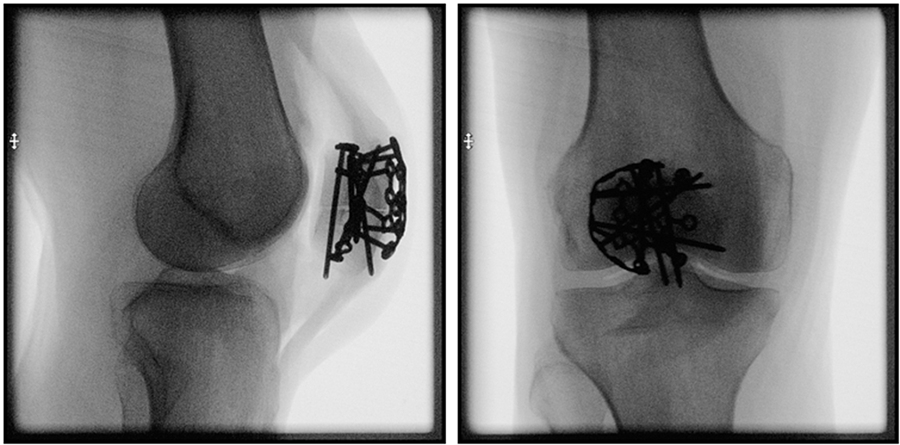

Treatment of both simple and complex patella fractures is a challenging clinical problem. It aims to restore the integrity of the extensor mechanism and the congruity of patellofemoral joint. Controversy exists regarding the most appropriate fixation method. Tension band wiring – aiming to convert tensile forces on the anterior aspect of the patella into compression forces across the fracture site – is the standard of care; however, it is associated with high complication rates. Recently, lateral rim variable angle locking titanium and steel plates have been developed for treatment of both simple and comminuted patella fractures (Fig 1). The low-profile plates have variable angle locking holes enabling up to 15° screw angulation to target small fracture fragments and to avoid fracture lines and other implants. They allow surgeons to achieve stable fixation in simple and complex patella fractures using bicortical, interfragmentary screws in a multiplanar fashion around the rim of the patella. These plates also minimize soft-tissue irritation and can be cut and contoured with dedicated instruments according to the patient anatomy and various fracture patterns. Sutures can be placed through the plate windows to anchor soft tissues to augment the repair.

Sixteen pairs of human anatomical specimen, namly knees, were used to simulate either two-part transverse simple AO/OTA 34C1 or five-part complex AO/OTA 34C3 patella fractures by means of osteotomies, with each fracture model being created in six pairs. The complex fracture pattern was characterized by a medial and a lateral proximal fragment, together with an inferomedial, an inferolateral and an inferior fragment mimicking comminution around the distal patellar pole. The specimens with simple fractures were pairwise assigned for fixation with either tension band wiring through two parallel cannulated screws, or a lateral rim variable angle locking plate. The knees with complex fractures were pairwise treated with either tension band wiring through two parallel cannulated screws plus circumferential cerclage wiring, or a lateral rim variable angle locking plate (Fig 2).